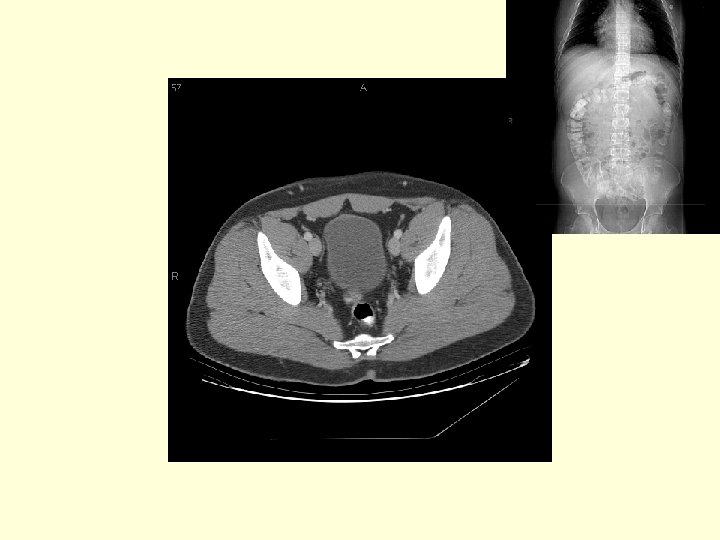

What vascular structures are marked by the arrows? The external iliac arteries and veins

What is this fluid filled structure? The bladder What portion of bowel is this located posterior to the bladder and anterior to the sacrum? The rectum What is the significance of the space between the bladder and the sacrum? This is the most dependent portion of the peritoneal cavity in a male.